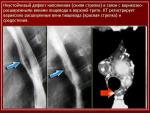

Диафрагмальные грыжи.

Варикозное расширение вен пищевода.